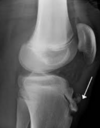

40

Dx?

Osgood schlatter disease